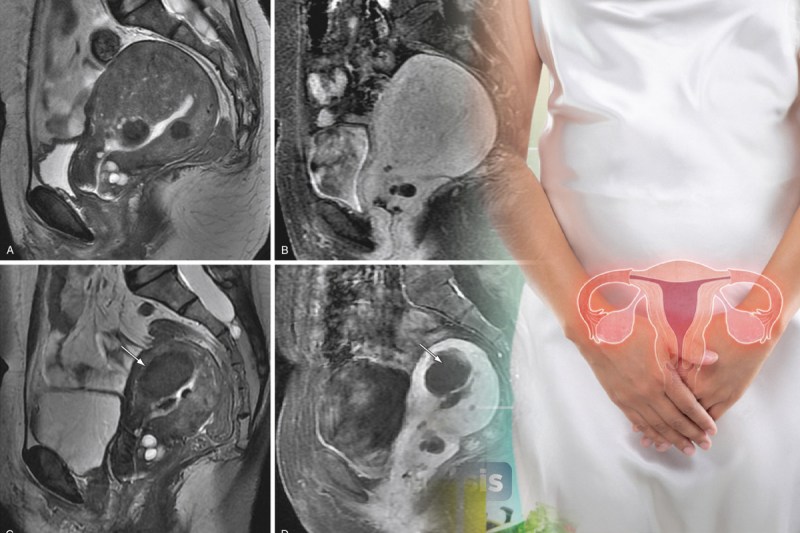

ऐडेनोमायोसिस महिलाओं में होने वाली ऐसी बीमारी है जिसमें गर्भाशय की मांसपेशियों के भीतर के लाइनिंग टिश्यू (एंडोमीट्रियम) का स्थानान्तरण गलत जगह पर होने से गर्भाशय की मांसपेशियों में सूजन आ जाती है।

ऐडेनोमायोसिस का कारण अज्ञात है। हालांकि गर्भाशय ट्रोमा को इस प्रकार के साथ संबद्ध किया गया है कि गर्भाशय की भीतर लाइनिंग और मांसपेशियों के बीच की बाधा को तोड़ सकते हैं जो सिजेरियन, ट्यूबल बंधाव, गर्भावस्था समाप्ति के रूप में होता है।